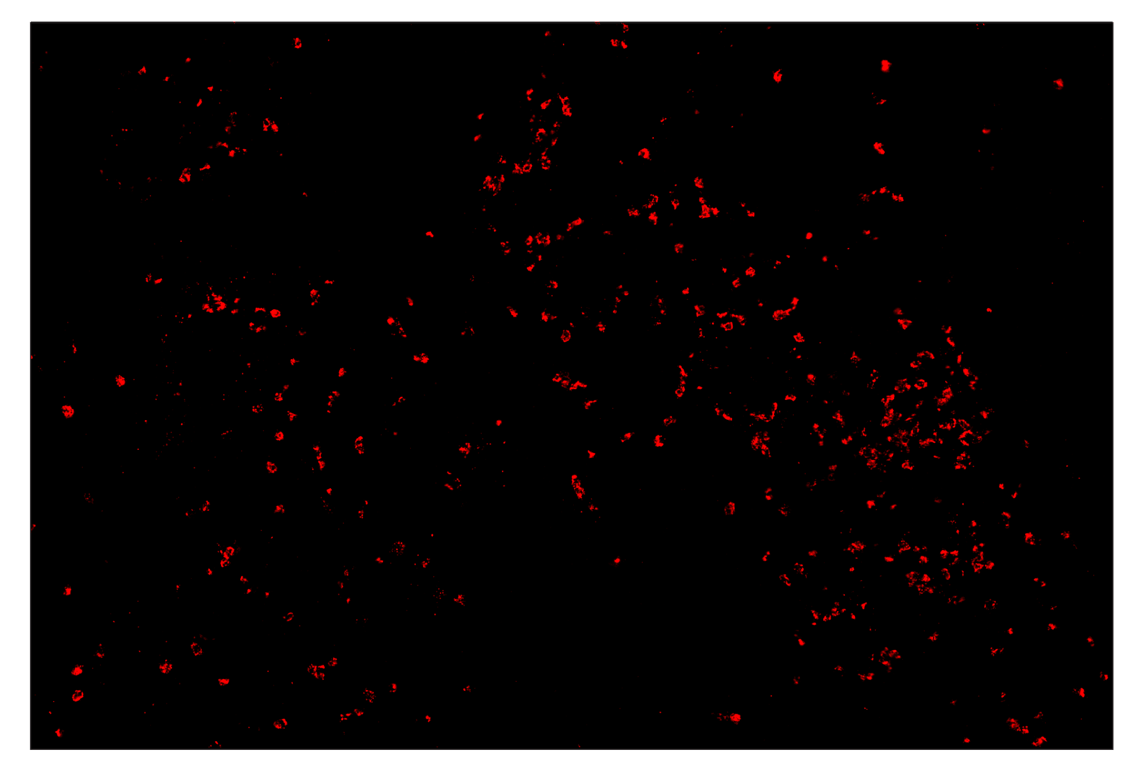

SignalStar™ multiplex immunohistochemical analysis of paraffin-embedded human lung adenocarcinoma using Myeloperoxidase (E1E7I) & CO-0138-647 SignalStar™ Oligo-Antibody Pair #53259 (red). All fluorophores have been assigned a pseudocolor, as indicated. Staining was performed on the BOND RX autostainer by Leica Biosystems.

Immunohistochemistry Image 4: Myeloperoxidase (E1E7I) & CO-0138-750 SignalStar<sup>™</sup> Oligo-Antibody Pair